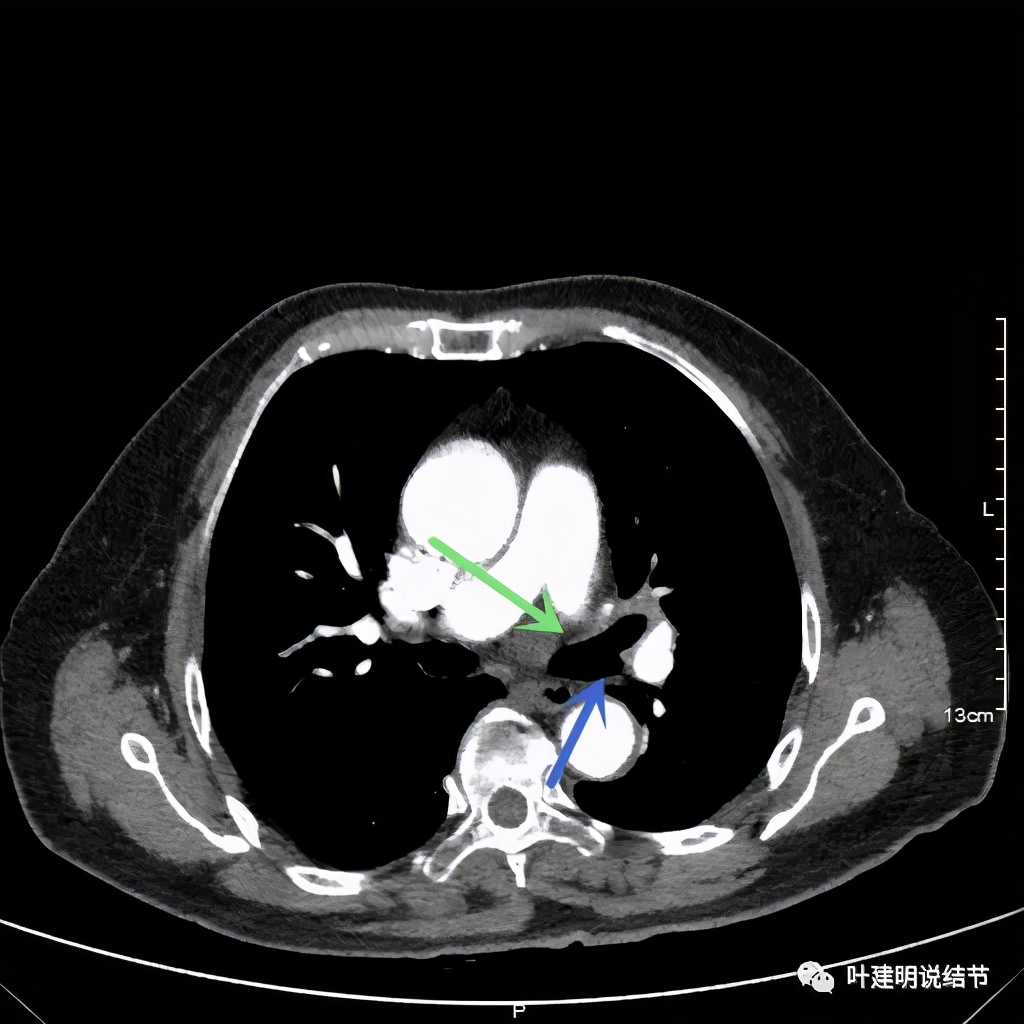

上图桔色箭头示左肺动脉分支处仍被软组织(原肿瘤所在)包绕,粉色箭头示肺动脉仍与肿瘤处关系密切

上图也示桔色箭头示左肺动脉分支处仍被软组织(原肿瘤所在)包绕,粉色箭头示肺动脉仍与肿瘤处关系密切

上图示肿瘤部位仍与肺动脉关系密切,似乎未能脱开,红色示肿瘤处

上图示左上叶开口已经显露出来

上图绿色示左上叶支气管,蓝色示下叶支气管开口处